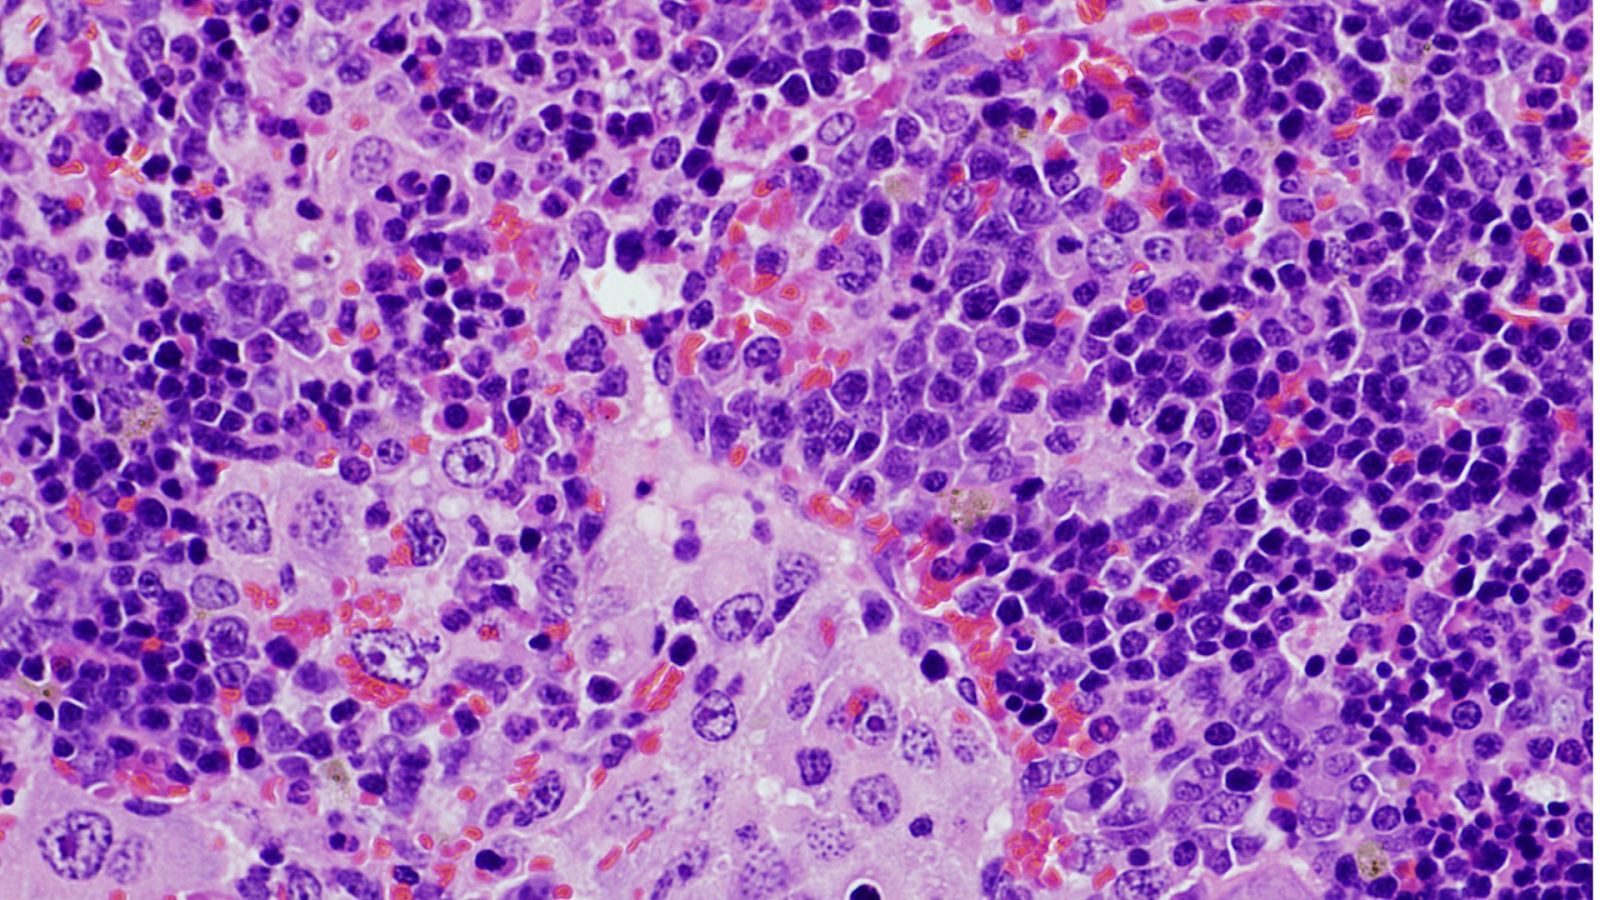

Imagen de microscopía de un bazo que presenta un linfoma

Un ejemplo de este proceso se desarrolla cuando la alteración en VAV1 se mezcla con la eliminación del gen antitumoral TRP53, que provoca el rápido desarrollo de un tumor muy específico de linfocitos T, conocido con el nombre de linfoma periférico de células T.